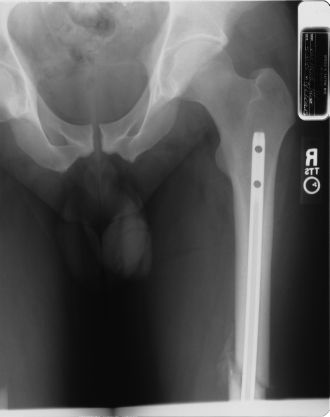

QuoteAt any rate- I must respond to Titanium Legs as I feel like he may be in the dark on something.....

Oh, I'm quite aware of what's in my x-rays. If you're really lucky, and maybe ask really nicely, I'll send you the very clear side view

QuoteSorry TitaniumLegs, its funny what you can see in an xray, unless of course its yours.

Oh, I think it's funny, too. Those x-ray tables and rooms are really cold!!

Lieutenant Dan!!!!

You got new legs! .... Magic Legs!